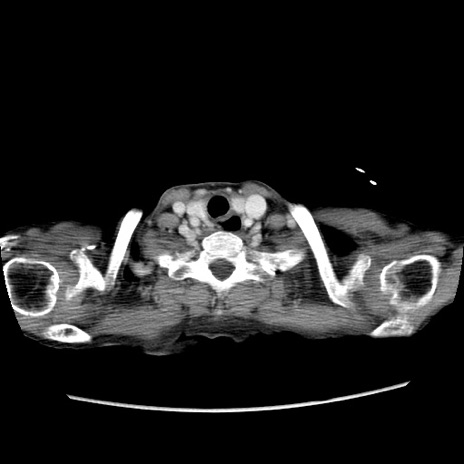

冠状断像